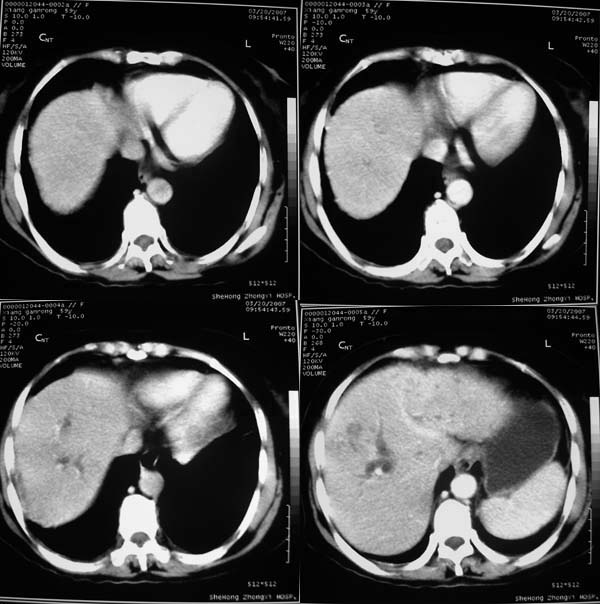

以下是引用汪涛同志在2007-3-25 15:26:00的发言:[br]1胆囊癌侵犯肝脏并门脉癌栓[br]2巨块型肝癌合并出血不除外

以下是引用yuhg在2007-3-25 17:31:00的发言:[br]考虑胆囊癌侵犯肝脏可能性大,因为病灶最大部分在胆囊窝,胆囊壁不规则明显增厚,肝内胆管扩张,胆总管受侵犯,肝内见转移灶,强化也支持胆囊癌,肝癌引起阻黄较少

以下是引用expert在2007-3-25 21:06:00的发言:[br]胆囊ca外侵,累及肝左叶,肝门明显受压,致肝内胆管梗阻扩张,伴肝右叶结节转移